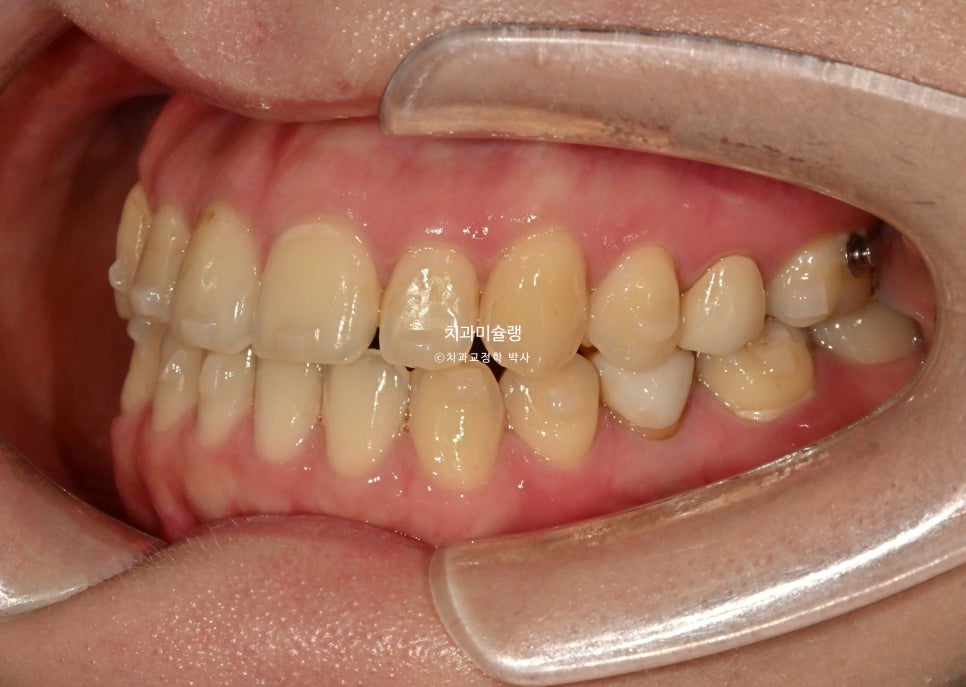

2024년 9월 초기 상담

작년 9월, 말할때 앞니가 안보여서 보이게 하고싶다 는 주소로 온 30대 환자분 입니다.

우측 송곳니가 내려와있고 앞니 치축이 위아래 둘다 전반적으로 기울어져 있습니다.

치아색도 어두운 편이고 갈색 반점이 넓게 퍼져있습니다.

내려와있는 한쪽 송곳니, 기울어진 치축 때문에 비대칭의 느낌이 있습니다.

말할때 윗니가 잘 안보이며 입술이 얇고 볼륨감이 적은편입니다. 웃을때도 치아가 그림자져 보입니다.